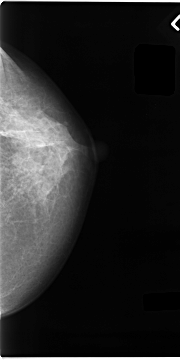

C_0061_1.LEFT_CC

LEFT_CC LINES 4680 PIXELS_PER_LINE 2336 BITS_PER_PIXEL 12 RESOLUTION 50 NON_OVERLAY